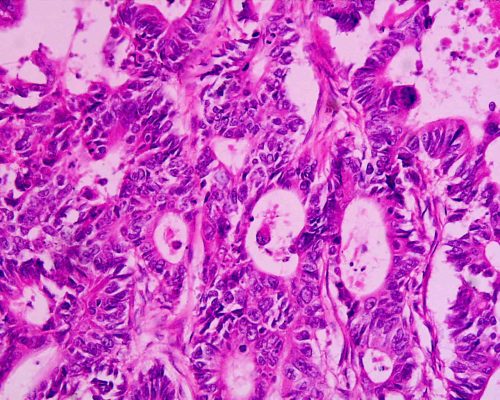

Nem, a megbízható és pontos szűrés a klinikánkon nem pusztán egy laboratóriumi székletvizsgálatot jelent. A végbélrák biztos kizárásához vagy a rákmegelőző állapotok (például polipok) felismeréséhez a vastagbél alsó 15-20 centiméteres szakaszának műszeres, tükrözéses vizsgálatára (rektoszkópia) van szükség. Ez a módszer ad azonnali, tiszta vizuális képet az orvos számára.